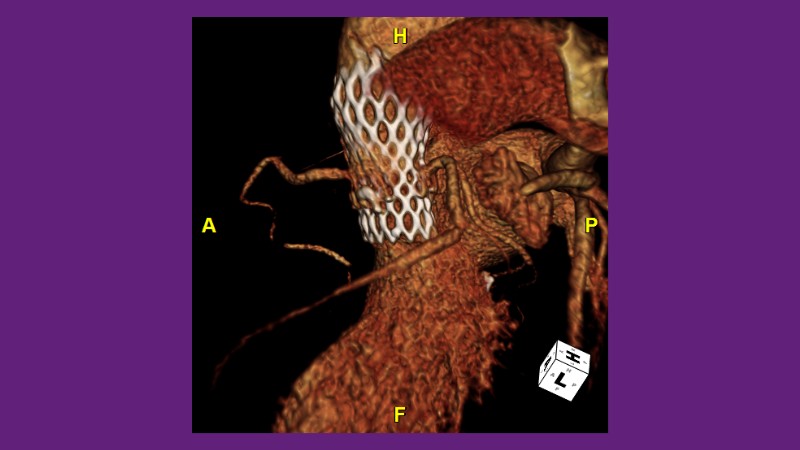

Standardised implant technique with self-expandable valve

Don’t miss this PCR Tokyo Valves 2025 session replay, where leading experts share key techniques for simplifying and optimising TAVI procedures with the Evolut device. This session covers essential insights into safely performing procedures on patients with various anatomical types using the self-expandable valve, while emphasising the importance of long-term patient care and outcomes. Discover valuable strategies for surgical explantation of transcatheter aortic bioprostheses, coronary cannulation, and commissural alignment post-TAVR. Learn expert tips for streamlining procedures, such as semi-rapid pacing, using Dryseal long, and skipping pre-BAV to improve TAVI results. Watch now to stay ahead in the field!